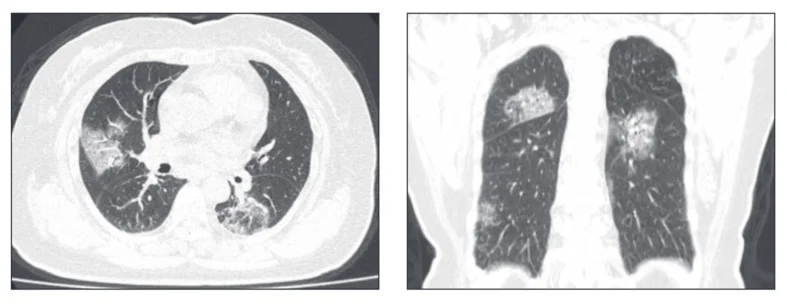

Для большинства патологий достаточно выполнения ультразвукового исследования легких в 6 зонах, описанного Д. Лихтенштейном (известное как Blue Protocol), или исследования легких по 8 точкам, описанного Дж. Вольпичелли. Однако анализ КТ-сканов у пациентов с COVID-19 показывает, что повреждения при этом заболевании являются мультифокальными и могут локализоваться в любой части легкого.

Выполняя ультразвуковое исследование легких в 6 зонах, велика вероятность пропустить патологию у пациента с COVID-19. Ультразвуковое обследование легких в 12 зонах повышает чувствительность к обнаружению поражений органа при COVID-19. Данный протокол был предложен итальянскими и китайскими специалистами (Buensenso, 2020 и Peng, 2020).

Китайской группой по УЗИ для интенсивной терапии (CCUSG) был просуммирован ранний опыт ультразвукового исследования легких для оценки инфекции SARS-CoV-2 в Китае с целью предупреждения передовых специалистов отделений интенсивной терапии об использовании ультразвукового исследования легких для лечения COVID-19. Было произведено УЗИ легких на 20 пациентах с COVID-19, используя 12-зонный метод.

Характерные выводы включают следующее:

Наблюдаемые паттерны происходили в промежутке от легкого альвеолярного интерстициального паттерна до тяжелого двустороннего интерстициального паттерна и консолидации легких. В таблице 1 приведены типичные результаты УЗИ легких у пациентов с респираторным заболеванием COVID-19 в сравнении с данными КТ грудной клетки.

Ниже представлен ряд изображений патологических изменений, которые Вы можете увидеть при УЗИ легких пациентов с COVID-19. Эти изменения можно найти в любой части легкого, поскольку COVID-19 имеет мультифокальное распределение. Возможно сочетание областей нормального легкого и области с патологией. Патологические изменения легких могут отсутствовать в начале заболевания и при легком течении COVID-19, однако, по мере его прогрессирования, Вы можете наблюдать всё больше патологических изменений.

Ниже приведены примеры УЗ-картины легких пациентов с COVID-19.